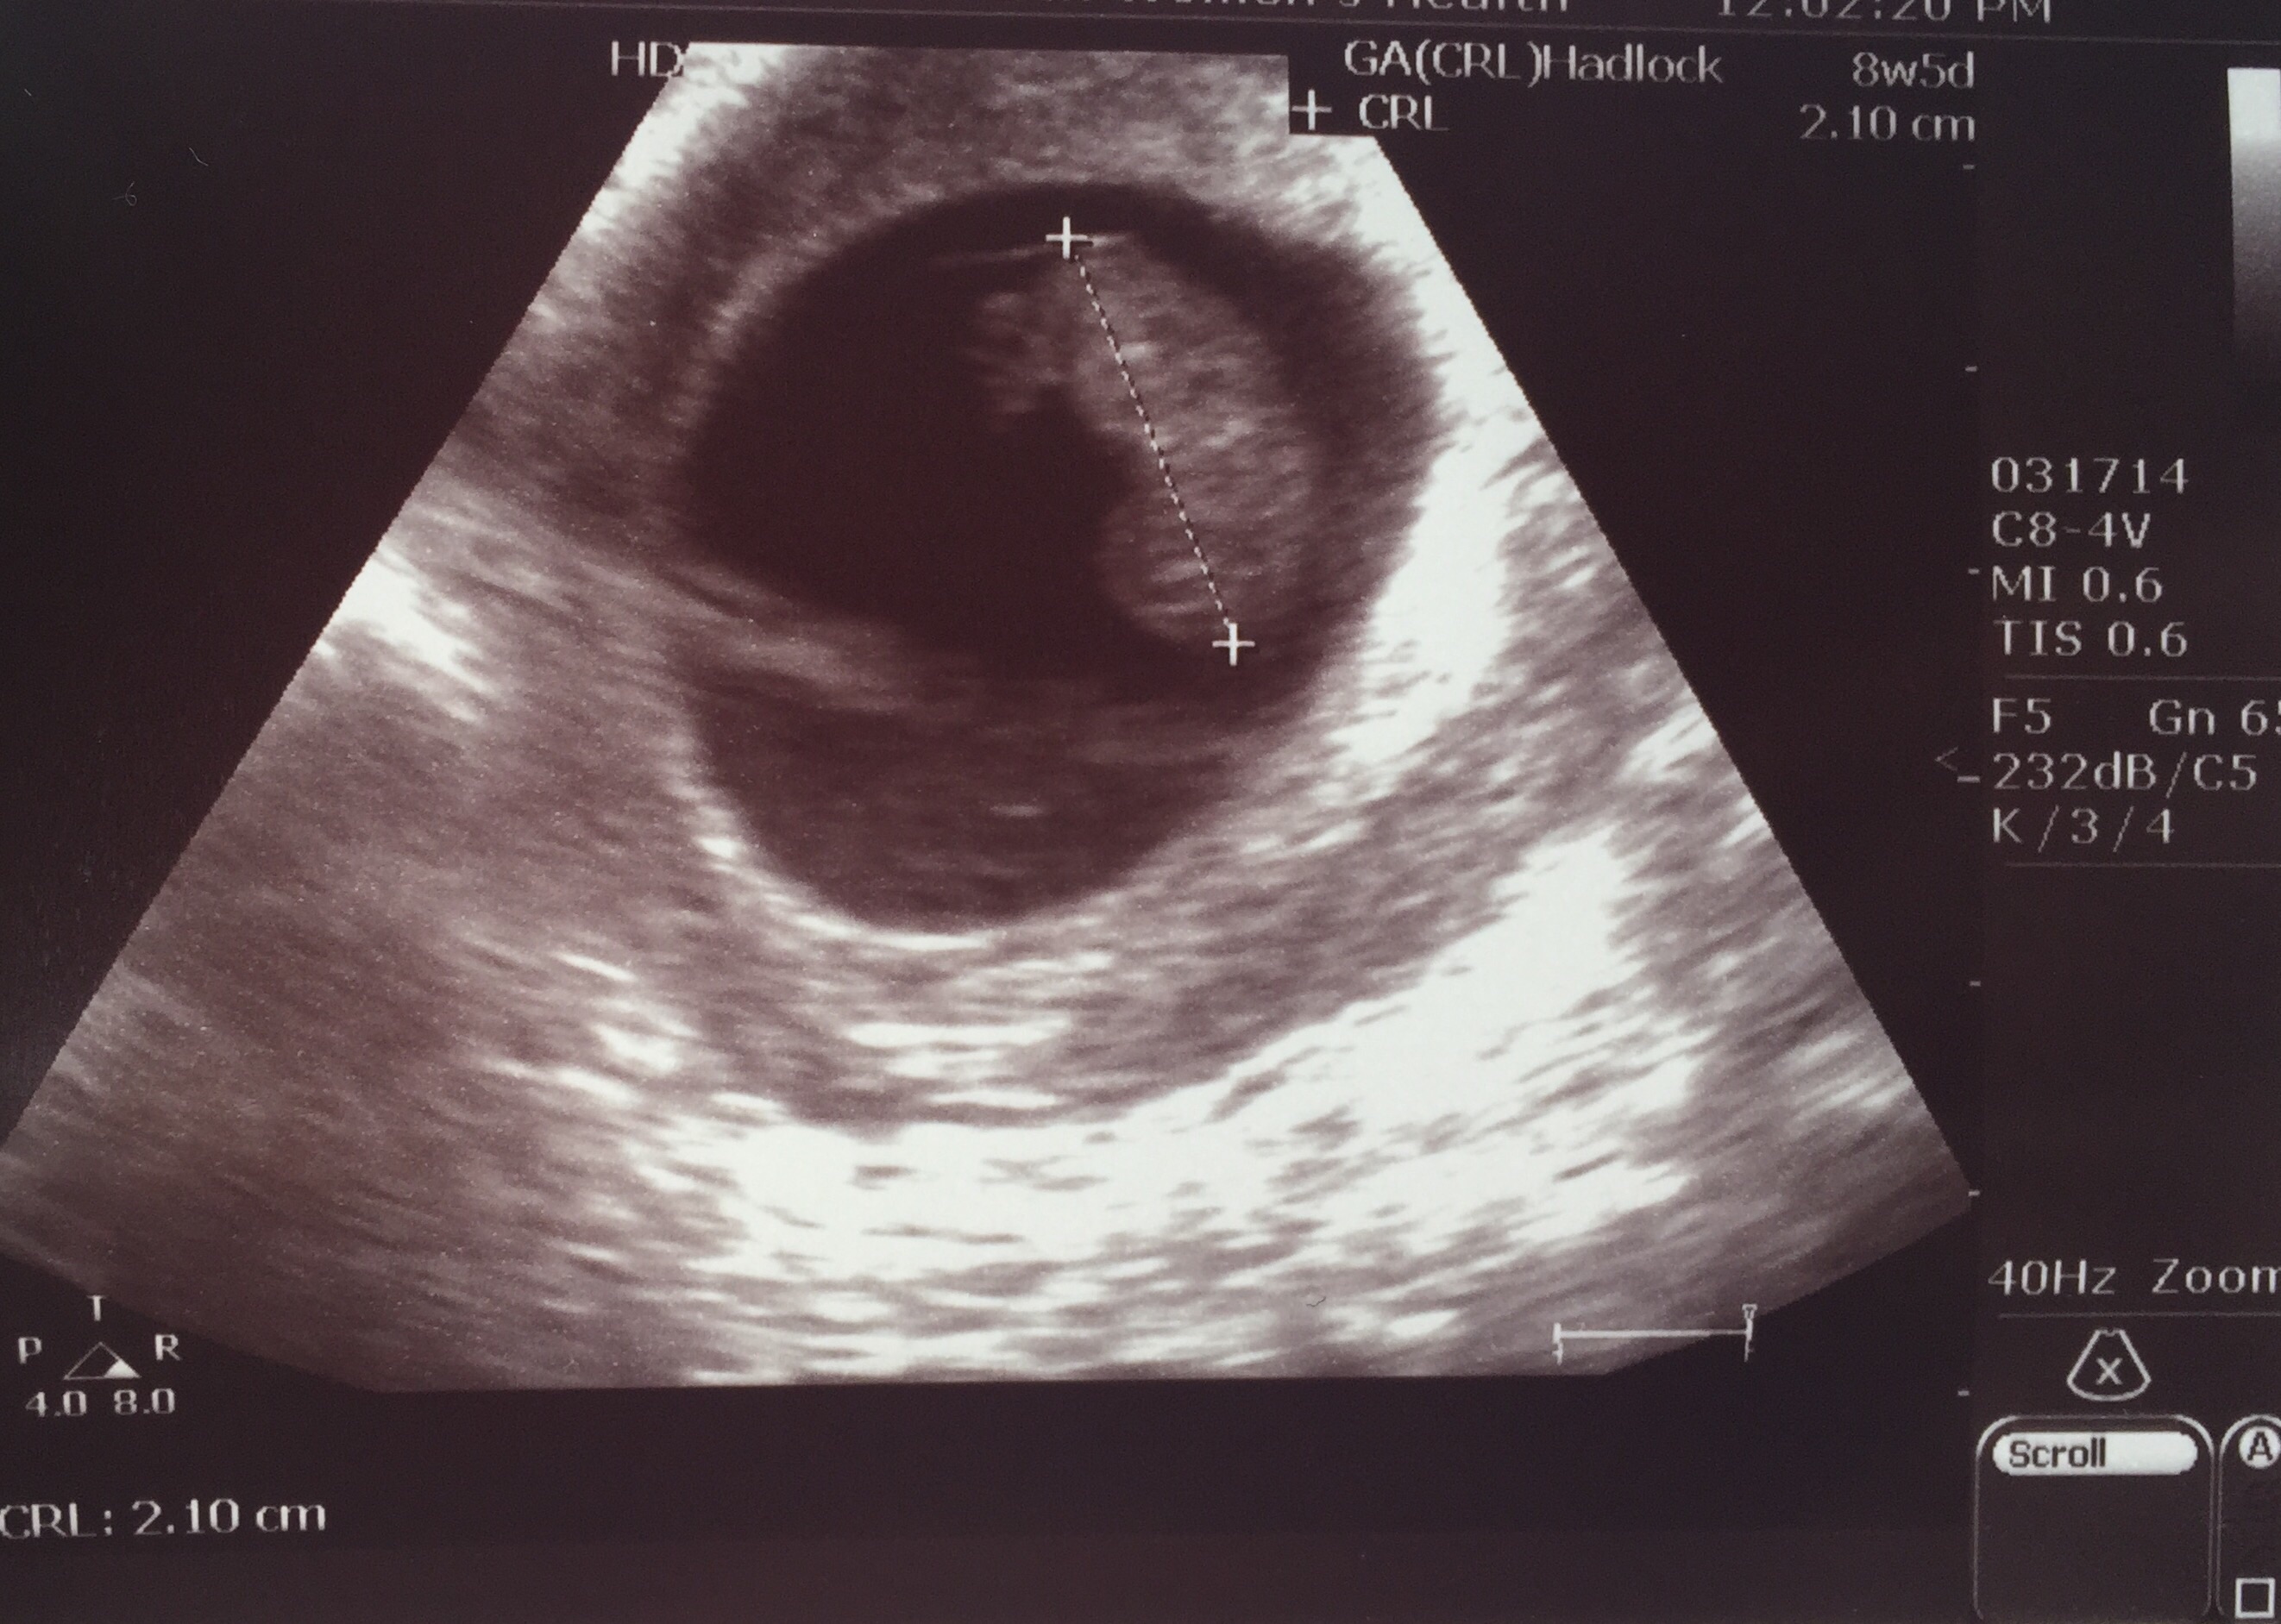

• I can finally join the club! We were finally able to see and hear our little one today. We're measuring 10w, like we thought. Super relieved that all is well!

• I have another ultrasound picture to share! Last time we were around 7 weeks, here I'm 8w6d!!! It was a crappy old machine, but she guessed the heartbeat was about 160 and we got to hear it again!!! So so so happy! For all you ladies that have symptoms that come and go, here's some hope for you because everything was fine even though my nausea and sore boobs have mostly stopped. Good luck!!!

• Our little gummy bear today at 9w2d with a heart rate of 172 :)

• Saw our blob for the 3rd time today, at 8w6d. Measuring right on target and hb of 173. Teared up again as per usual, ha!

• I'm 10 weeks today. My due date is April 7th. This picture is actually from my second ultrasound that I got yesterday. I got my first one done at 7 weeks and 5 days due to some minor bleeding which they determined was from a small blood blister in my uterus. As of yesterday we got the good news that the blood blister has shrunk dramatically! So now my appointments will continue on as normal. The baby's heartbeat was 156 at my first appointment and yesterday it was 175. I'm not sure I can accurately describe how happy I was to see my little baby moving around on the screen yesterday! It's truly something magical.